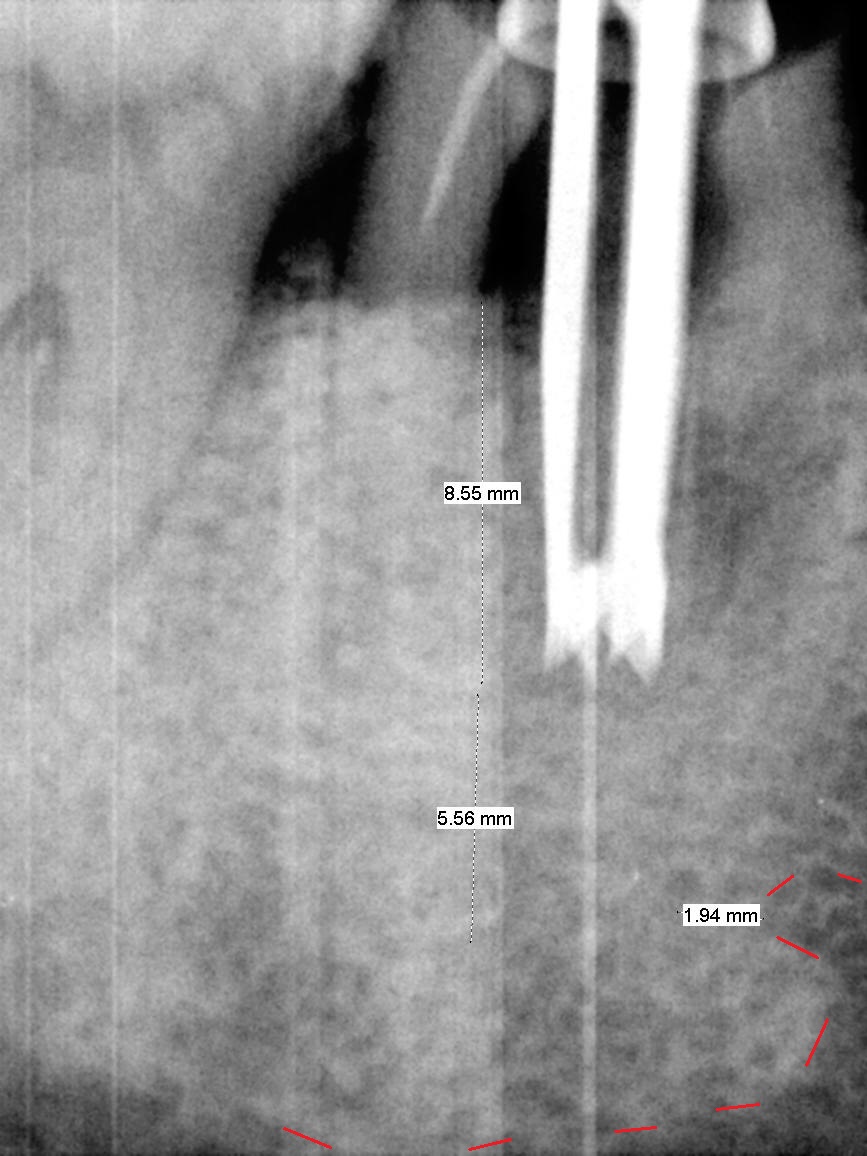

After cleaning the root surface with a surgical curette, a 1.6 mm pilot drill is used to start osteotomy (O) between the mesial (M) and distal (D) roots, followed by a marking bur and 3.8 mm Magic drill 13 mm deep (Fig.1,2). Following root removal, the 3.8 mm drill is reused for 11 mm (Fig.3). After deepening the osteotomy for another 2 mm, a 4.5x13 mm implant is placed with insertion torque of 50 Ncm, followed by allograft (*, .5-2 mm) and a 5x4(2) mm abutment (Fig.4,5). An immediate provisional is fabricated to close the socket (Fig.6 P (lock in)). The detached buccal gingiva (Fig.6 *) is kept in place by applying periodontal dressing (Fig.7 *). Red dashed lines in Fig.1, 3, 5 represents the superior border of the Inferior Alveolar Canal and Mental Foramen.